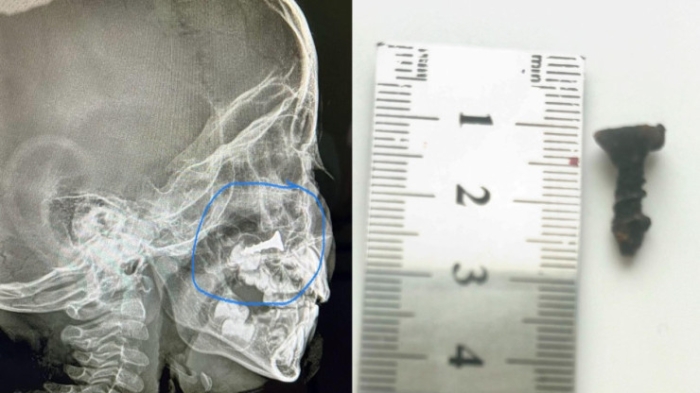

5. Ребенок полгода жил с шурупом в носу на юге Казахстана

Tengrinews.kz подготовил дайджест главных и самых интересных новостей за четверг, 7 ноября. Президент Касым-Жомарт Токаев освободил от должностей двух членов Центральной избирательной комиссии (ЦИК) — Сабилу Мустафину и Константина Петрова. Новыми членами ЦИК Президент назначил Азамата Айманакумова и Михаила Бортника. Сабила Мустафина и Констатин Петров. Фото:gov.kz Сегодня Глава государства принял министра иностранных дел России Сергея Лаврова. В ходе беседы особое внимание было уделено подготовке к предстоящему государственному визиту президента России Владимира Путина в Казахстан, который запланирован на 27 ноября. Фото пресс-службы Акорды На Астану обрушился ураганный ветер, который сносил целые конструкции, валил деревья и фонарные столбы, повредил автомобили и детские площадки, срывал облицовку с домов. Социальные сети заполонили фото и видео последствий разгулявшейся стихии. Подробнее — в материале. Читайте также: “Нормально прошел штормовой день“ — аким Астаны об ураганном ветре Депутат Сената от Алматинской области Жанболат Жоргенбаев прокомментировал появившуюся в соцсетях информацию о родстве с арестованным Хасаном Касымбаевым, которого в Талгаре называют главой «Хуторской бригады». В частности, сенатор подтвердил родство с Касымбаевым, заявив, что Хасан является его «дальним родственником». «У казахов, как вы знаете, родственников всегда очень много. Но мы не поддерживали каких-либо постоянных контактов», — заявил депутат. Хасан Касымбаев, Жанболат Жоргенбаев. Кадр из видео, senate.parlam.kz Акима Астаны Жениса Касымбека попросили изменить рабочий график для горожан из-за перевода времени. На встрече акима с жителями района Байконур один из горожан заявил, что, раз вернуть прежний часовой пояс нельзя, стоит изменить рабочий график. Врачи областной многопрофильной детской больницы извлекли из носа малыша шуруп. Он находился в носовой полости полгода. Как рассказал заведующий отделением экстренной хирургии областной многопрофильной детской больницы Болат Маханбетияров, инородное тело обнаружили случайно, когда мама привела ребенка на рентген. Фотографии предоставлены врачами областной многопрофильной детской больницы Кызылорды В Карагандинской области 65-летний пенсионер скончался от инфаркта после задержания сотрудниками полиции. Родные пенсионера считают, что участковые инспекторы превысили свои должностные полномочия. По их словам, они составили на погибшего протокол о распитии алкоголя в общественном месте, хотя именно в тот день мужчина спиртное не употреблял. В Павлодарской области из-за сильного ветра рухнуло дерево и упало на проходившую рядом женщину. К сожалению, пострадавшая скончалась в результате полученных травм, которые оказались несовместимы с жизнью. В Министерстве по чрезвычайным ситуациям перечислили сейсмоопасные регионы Казахстана. По данным ведомства, наиболее сейсмически опасными регионами считаются юг и юго-восток страны: Алматинская, Туркестанская, Жамбылская, Кызылординская области, Алматы и область Жетысу. В Жуалынском районе Жамбылской области полиция задержала водителя из Алматинской области, который управлял автомобилем с закрытыми государственными номерами. Машина была остановлена на 564-м километре трассы Западная Европа – Западный Китай. Водитель закрыл буквы на номерах красной бумагой. Он перевозил товар из Ташкента в Алматинскую область. Российский рэпер Тимур Юнусов, известный как Тимати, поделился историей о том, как познакомился с P.Diddy через загадочного мужчину из Казахстана. Музыкант побывал на двух вечеринках американской звезды. Подробности истории в материале Tengri Life. Фото: depositphotos.com / s_bukley Фото vk.com / @timatiofficial